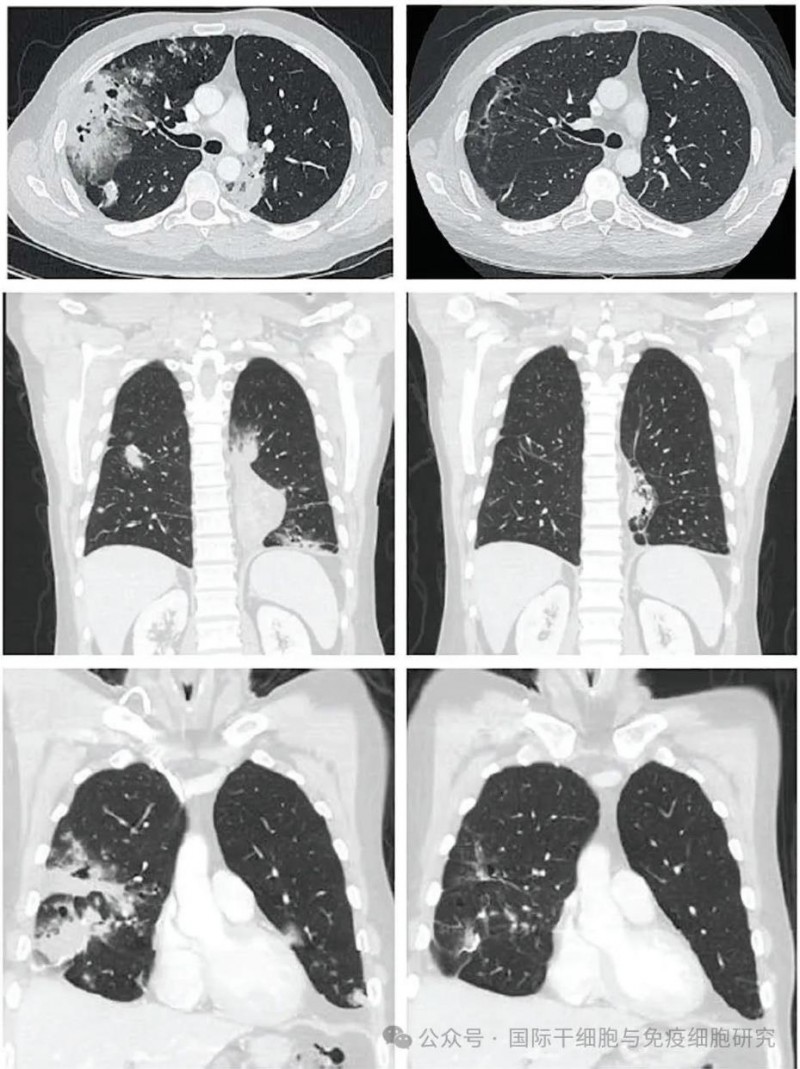

其中,一位41岁的男性IV期肺黏液腺癌患者,在TIL治疗前、TIL治疗6周后复查CT发现,反应持续时间为1.1+至26.2+个月。随着时间的推移,反应加深。在TIL输注后12周,根据RECIST v1.1标准,达到81%的部分缓解(PR)(详见下图)。

▲图源“Cancer Discov”,版权归原作者所有,如无意中侵犯了知识产权,请联系我们删除